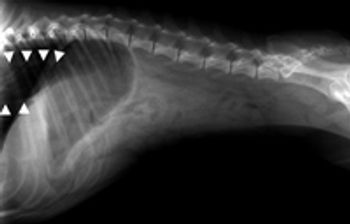

A 2-year-old intact male Boston terrier was evaluated because of a recent onset of gagging and vomiting.